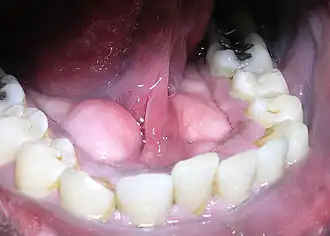

Les tori mandibulaires (torus au singulier) sont des excroissances osseuses inconstantes s'apparentant à des tumeurs bénignes de la face postérieure du corps de la mandibule.

Les tori mandibulaires sont généralement présents près des prémolaires et au-dessus de l'insertion du muscle mylo-hyoïdien[1].